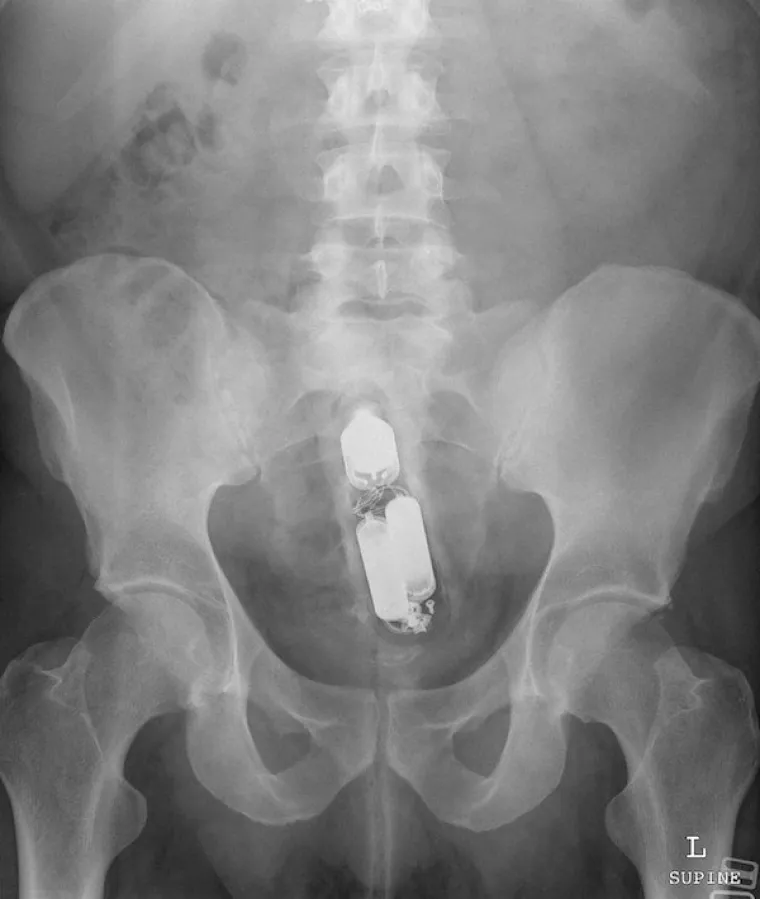

Vibrator.